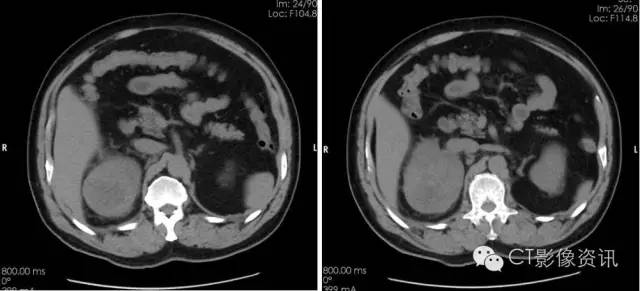

分泌期及排泄期可见病灶不均匀强化,对比与周围明显强化的肾脏组织,病灶边界清晰,实质内有不规则低密度坏死区。